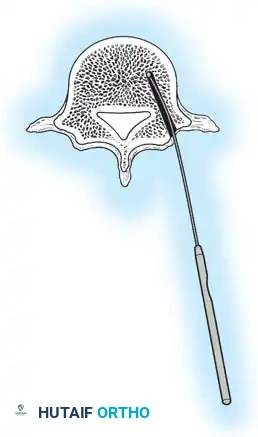

The Moe Technique (Lumbar Spine)

In the lumbar spine, the facet joints are oriented in a more sagittal plane, necessitating a modified approach.

Fig. 38-27: The Moe technique adapted for lumbar facet fusion, addressing the sagittal orientation of the joints.

- Utilize a small osteotome or a needle-nose rongeur to resect the adjoining joint surfaces.

- This creates a distinct rectangular defect within the sagittally oriented joint space.

- Pack this defect forcefully with cancellous bone graft.

- Proceed to decorticate the entire exposed posterior elements (laminae and transverse processes) using Cobb gouges, always directing force away from the spinal canal.